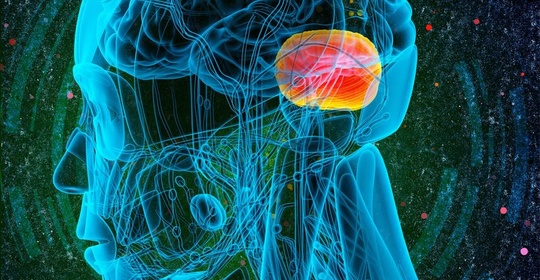

丘腦下部損害:冷敷護理與醫療干預

丘腦下部損害:緊急處理與注意事項